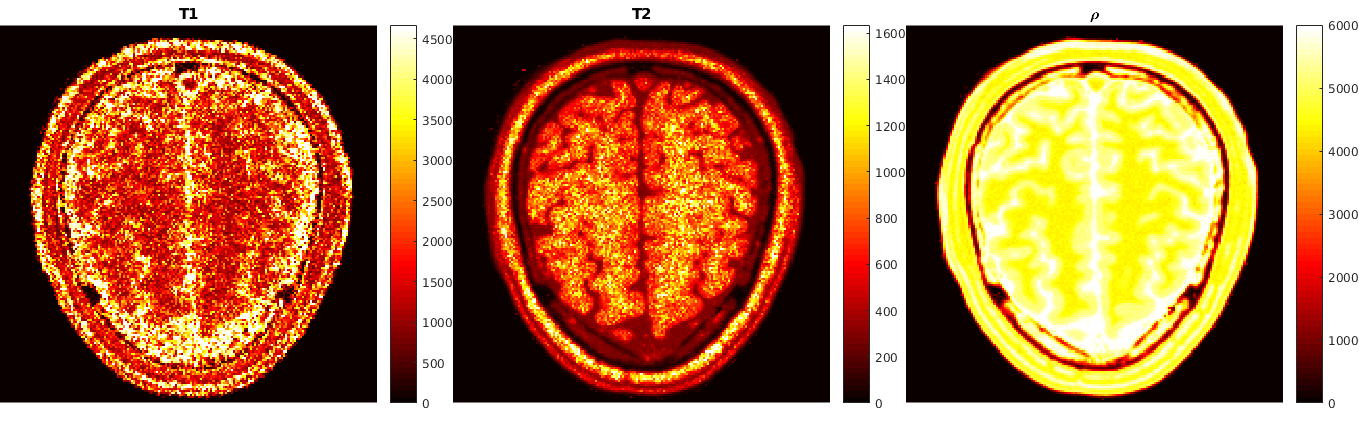

The second example comes from quantitative magnetic resonance imaging - qMRI. In this context, one integrates a mathematical model of the acquisition physics (the Bloch equations [16]) into the associated image reconstruction task in order to relate qualitative information (such as the net magnetization y=ρm𝑦𝜌𝑚y=\rho m) with objective, tissue dependent quantitative information (such as T1subscript𝑇1T_{1} and T2subscript𝑇2T_{2}, the longitudinal and the transverse relaxation times, respectively, or the proton spin density ρ𝜌\rho). This model is then used to obtain quantitative reconstructions from subsampled measurement data g𝑔g in k-space by a variational approach. The provision of such quantitative reconstructions is highly important, e.g., for subsequent automated image classification procedures to identify tissue anomalies. Moreover, in [16] it is demonstrated that such an integrated physics-based approach is superior to the state-of-the-art technique of magnetic resonance fingerprinting (MRF) [32] and its improved variants [14, 34]. Specifically in MRI, acquisition data are obtained at different pre-specified times (read-out times) t1,,tLsubscript𝑡1subscript𝑡𝐿t_{1},\ldots,t_{L}, during which the magnetization of the matter is excited through the control of a time dependent external magnetic field B𝐵B. Given u=(T1,T2,ρ)𝑢subscript𝑇1subscript𝑇2𝜌u=(T_{1},T_{2},\rho), the magnetization time vector at t1,tLsubscript𝑡1subscript𝑡𝐿t_{1},\ldots t_{L} is then given by y=Π(u)𝑦Π𝑢y=\Pi(u), where ΠΠ\Pi denotes the solution map associated with a discrete version of the Bloch equations. Crucial to this approach is the fact that, at least for specific variations of the external magnetic field B𝐵B, explicit formulas for the solution map of the Bloch equations are available. For instance, in [14] and [16] Inversion Recovery balanced Steady-State Free Precession (IR-bSSFP) [41] is used which involves certain flip angle sequence patterns that characterize the external magnetic field B𝐵B. These flip angle patterns allow for a simple approximation of the solutions of the Bloch equations at the read-out times through a recurrence formula. However, in general, it is quite typical that for more complicated external magnetic fields one does not have at hand explicit representations for the Bloch solution map. More generally, for most nonlinear differential equations (including those relevant in image reconstruction tasks) explicit solution maps might be too complicated to obtain. However, one may employ numerical methods to approximate their solutions (yi)i=1nDsuperscriptsubscriptsubscript𝑦𝑖𝑖1subscript𝑛𝐷(y_{i})_{i=1}^{{n_{D}}} given a specific (coarse) selection of parameters (ui)i=1nDsuperscriptsubscriptsubscript𝑢𝑖𝑖1subscript𝑛𝐷(u_{i})_{i=1}^{{n_{D}}} within a certain range. This generates a data set D𝐷D which is then employed in a learning procedure to generate an ANN based approximation Π𝒩subscriptΠ𝒩\Pi_{\mathcal{N}} of ΠΠ\Pi. This gives rise to Q𝒩:=AΠ𝒩assignsubscript𝑄𝒩𝐴subscriptΠ𝒩Q_{\mathcal{N}}:=A\Pi_{\mathcal{N}} in (1.2) and requires an associated analytical as well as numerical treatment of the (reduced) minimization problem.